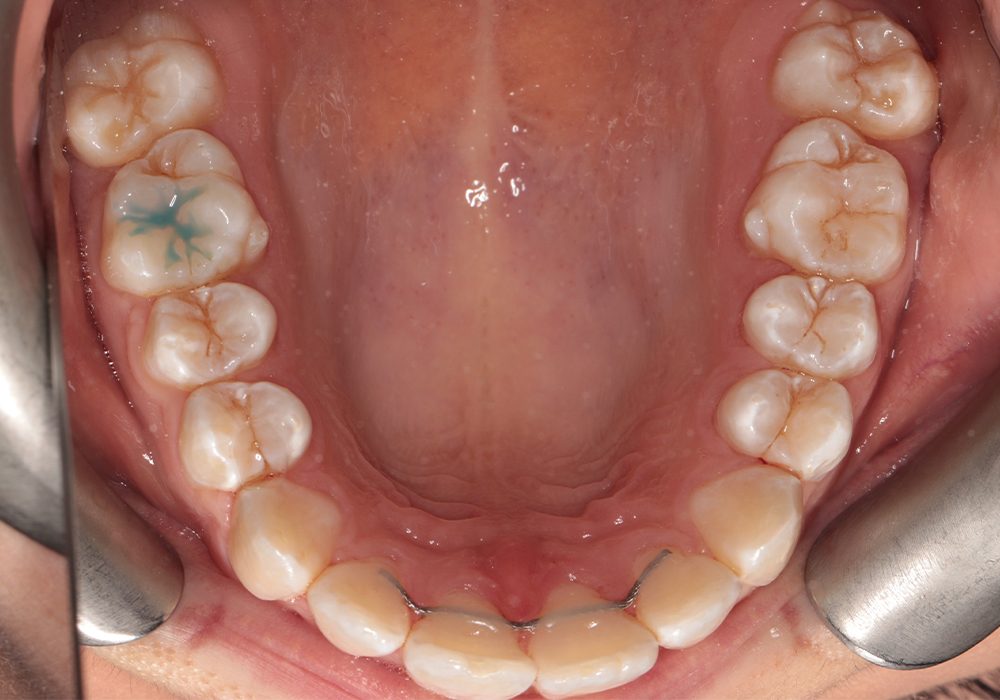

Przed copy

Przed